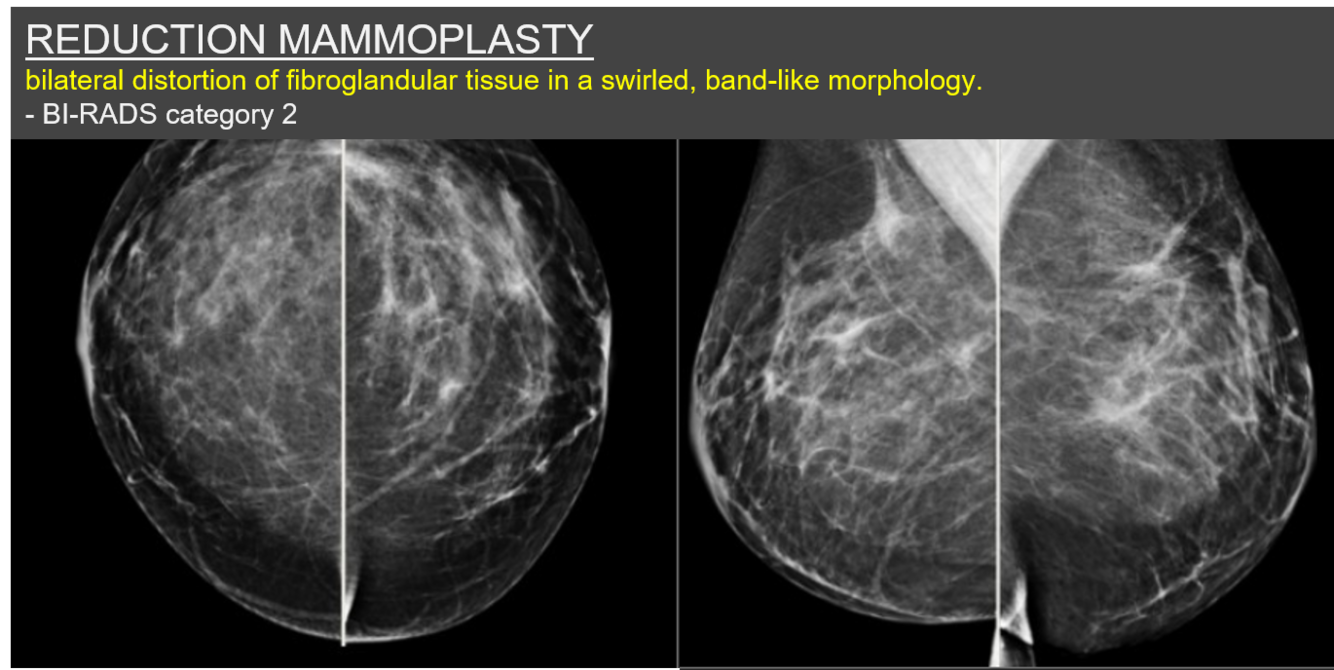

What clinical history most likely accounts for the imaging findings shown?

Bilateral reduction mammoplasty